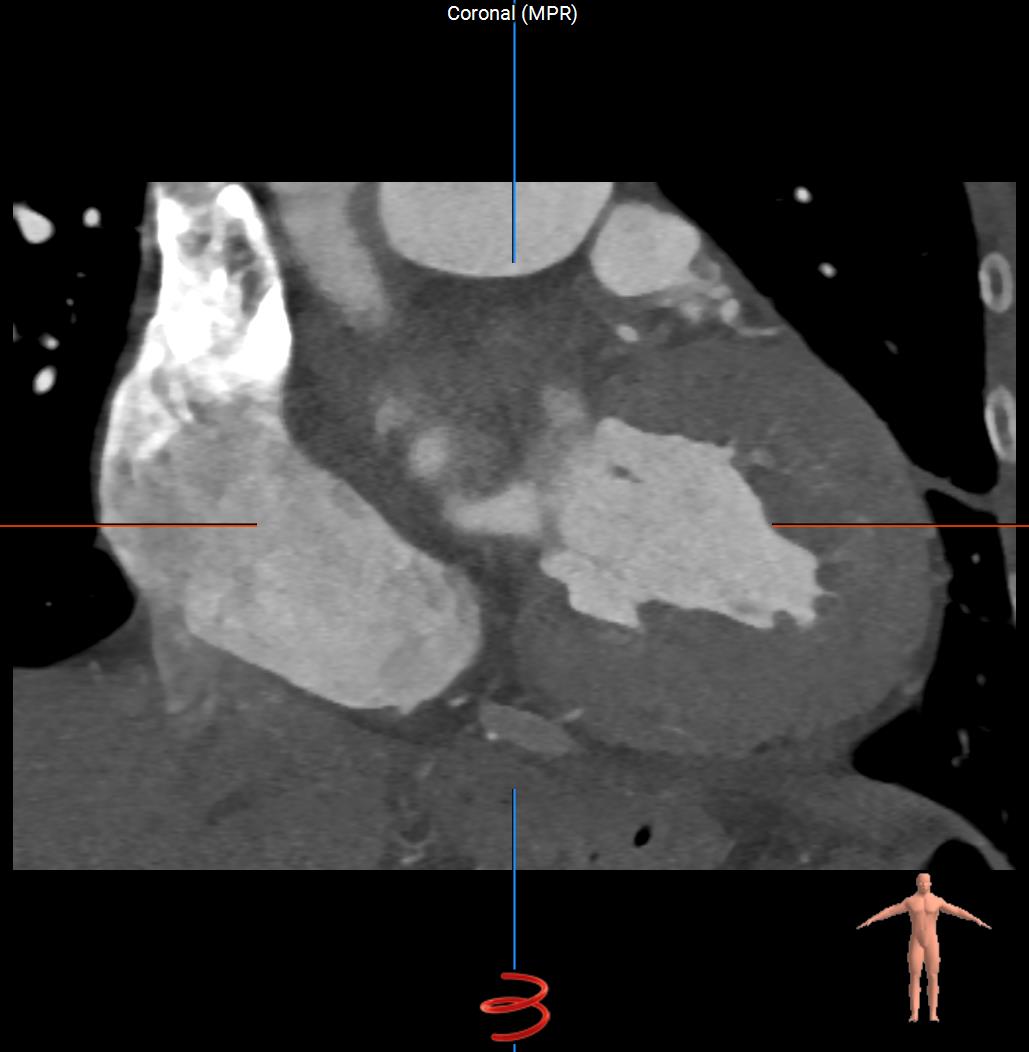

Sagittal-CT-Heart.jpgCoronal-CT-Heart.jpgAxial-CT-Heart.jpg